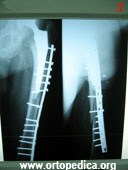

3. Вид после остеосинтеза пластинкой и шурупами